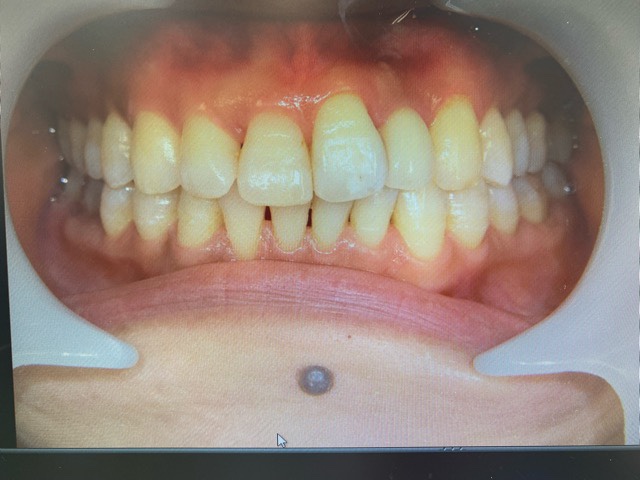

こちらの患者様歯元々お顔立ちが整っていて、お綺麗でした!が、歯並びが気になって上手く笑顔になれないご様子でした。

下の歯はインビザライン矯正を行い、上の歯はセラミッククラウンで治療させていただきました!

下の歯のガタガタや、歯の隙間 いわゆるブラックトライアングルも綺麗に治り、

上の歯の曲がった部分も、高さの違っていた歯肉の位置も、綺麗に整っているのがお分かりになると思います。